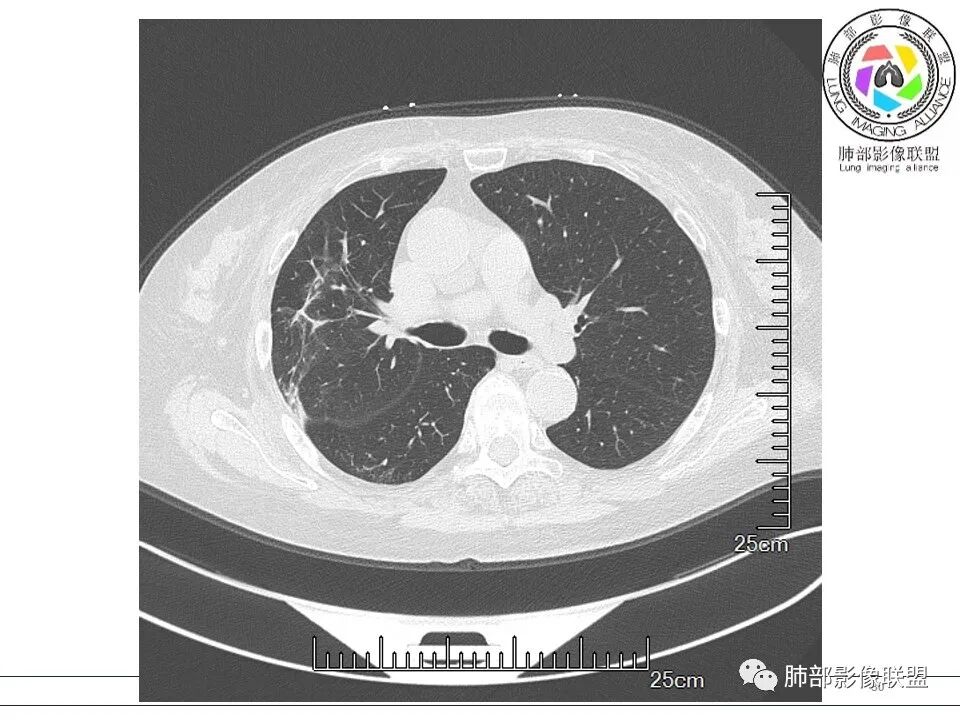

病例结果

隐球菌肺炎诊断要点

1、宿主:生活及工作环境中有无鸽子及鸟禽接触史,有无免疫缺陷背景(艾滋、化疗、器官移植、激素及免疫抑制剂使用史)。

2、类型:常见有孤立肉芽肿型、肺炎实变型、混合型(多发结节/实变/空洞)、弥漫粟粒/间质型。免疫正常宿主多表现为孤立肉芽肿型,也可以表现为肺炎实变型或混合型。免疫缺陷宿主则容易肺内播散形成多发(结节、实变、空洞)或弥漫粟粒/间质型,可累及中枢系统并发隐球菌脑炎。

5、分布:隐球菌肺炎是肺泡性炎症,病灶分布多位于胸膜下,可紧贴胸膜,也可与胸膜邻近,病灶长轴与胸膜平行。(划重点,分布特点非常重要,因为隐球菌如果没有荚膜,会被巨噬细胞吞噬,在人体内是无法生存。隐球菌孢子吸入后,要有高浓度的CO2的条件下,才能形成荚膜,所以肺泡内、胸膜下多见)

10、“葫芦兄弟”:邻近胸膜多发结节,形态接近,排列呈长串状。